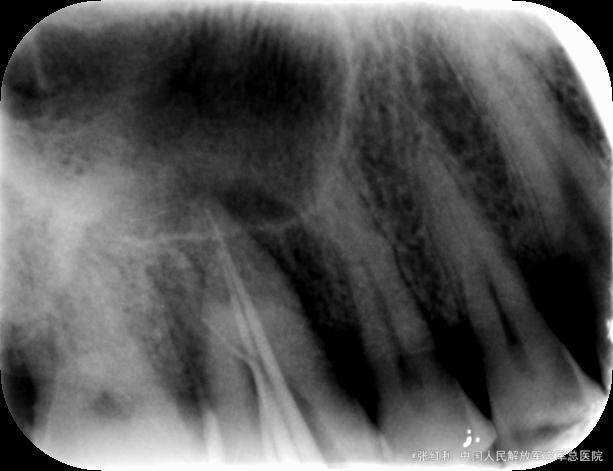

诊断:16牙周牙髓联合病变(逆行性牙髓炎) 治疗计划:16RCT+牙周基础治疗+改良翻瓣术 初诊:常规局麻下开髓揭顶,髓腔钙化,少量髓石,超声探查根管,拔髓,根管较细,疏通,封EDTA,一周后复诊。 复诊1:去暂封,继续探查根管,P、MB通畅,DB根尖区钙化,电测根长:P=MB=17.5mm,DB=15mm,EDTA下手扩+机扩+protaper根备至F2,生理盐水+双氧水反复交替冲洗,干燥,CP棉球+ZOE暂封,约日复诊。 复诊216消毒,局麻下洁治,刮治,小翻瓣术,搔刮出大量肉芽组织及少量牙石,根面平整,浓替硝唑冲洗,复位,OHI,约日复诊。 复诊3:腭侧窦道基本愈合,去暂封,超声荡洗,干燥,试尖可,糊剂+热牙胶根充,棉球+ZOE暂封,2周后复诊树脂充填。 复诊4:复诊常规树脂充填,腭侧窦道愈合(忘记拍片子,太遗憾,但是患者1个月后会过来复查)。

牙周牙髓联合病变的牙齿经常屋漏偏逢连夜雨,本身都已经很难治疗,还出现根管钙化不通,难以达到工作长度,但是遇到这种情况就放弃治疗了吗,当然不是,既然不通,可以不强行扩通,可以把目前能够做到的做到最好,看看预后,当然,这种情况得是病人理解并且配合,有的时候会有意想不到的收获,找个病例远中根尖没有到达工作长度,短期效果还是不错,期待长期效果,我还是抱了一定的希望的。